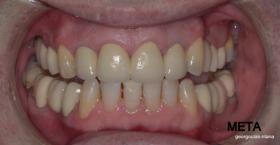

Ο ασθενής  προσήλθε στο ιατρείο μας θέλοντας να βελτιώσει την εμφάνιση των πρόσθιων δοντιών του και να αποκαταστήσει την υγεία κ την λειτουργία όλου του στόματος. Πραγματοποιήθηκε περιοδοντική θεραπεία κ ενδοδοντικές θεραπείες (απονευρώσεις) όπου κρίθηκε απαραίτητο και στη συνέχεια τοποθετήθηκαν 3 εμφυτεύματα, 2 δεξιά στις θέσεις του πρώτου κ δεύτερου γομφίου κ 1 αριστερά στη θέση του πρώτου προγομφίου. Κατά την  τοποθέτηση των 2 εμφυτευμάτων της δεξιάς πλευράς, πραγματοποιήθηκε κλειστή ανύψωση ιγμορείου με το σύστημα Piezotome-Intralift , τεχνική που εξασφαλίζει τη μικρότερη δυνατή επέμβαση κ τη μικρότερη μετεγχειρητική ταλαιπωρία (minimally invasive), καθώς κ αυξητικους παράγοντες PRF. Σε όλη τη διάρκεια της θεραπείας  ο ασθενής ήταν καλυμμένος τόσο αισθητικά όσο και λειτουργικά με προσωρινές μεταβατικές αποκαταστάσεις. 4 μήνες μετά την  τοποθέτηση των εμφυτευμάτων κ την οστεοενσωμάτωσή τους, ακολούθησε η τοποθέτηση των μόνιμων αποκαταστάσεων.